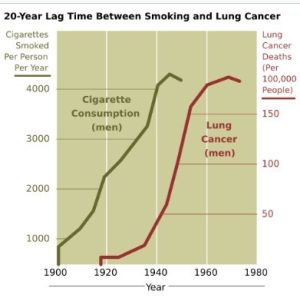

سیگار کشیدن

استعمال دخانیات، به ویژه سیگار تاکنون دلیل اصلی ابتلا به سرطان ریه بودهاست. دود سیگار حاوی بیش از ۶۰ ماده سرطانزا شناخته شدهاست از جمله ایزوتوپ پرتوزا ناشی از فرایند تجزیه رادون، نیترو آمین و بنزوپیرین. به علاوه، نیکوتین واکنش ایمنی بدن را در مقابل رشد سلولهای سرطانی در بافتهای آسیب دیده سرکوب میکند. در سراسر دنیا به خصوص در کشورهای توسعه یافته، ۹۰٪ از مرگ و میرهای ناشی از سرطان ریه در مردان در طول سال 2020 به استعمال دخانیات مربوط بودهاست (۷۰٪ برای زنان). کشیدن سیگار علت ۸۹–۹۰٪ از موارد ابتلا به سرطان ریه است. به نظر متخصصان سیگار احتمال ابتلا به این بیماری را تا ۲۰ برابر و آلودگی هوا تا دو برابر افزایش میدهد.

شکل 2. شکل نشان میدهد که چگونه افزایش کلی فروش محصولات تنباکو در ایالات متحده آمریکا در چهار دهه اول قرن ۲۰ (سیگار به ازای هر نفر در هر سال) به افزایش سریع نرخ سرطان ریه در طول دهه ۳۰، ۴۰ و ۵۰ منجر شدهاست (مرگ و میر ناشی از سرطان ریه در هر ۱۰۰٬۰۰۰ جمعیت آقا در هر سال)